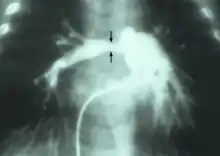

Stenosis of the right pulmonary artery in a patient which was due to a case of congenital rubella. | |